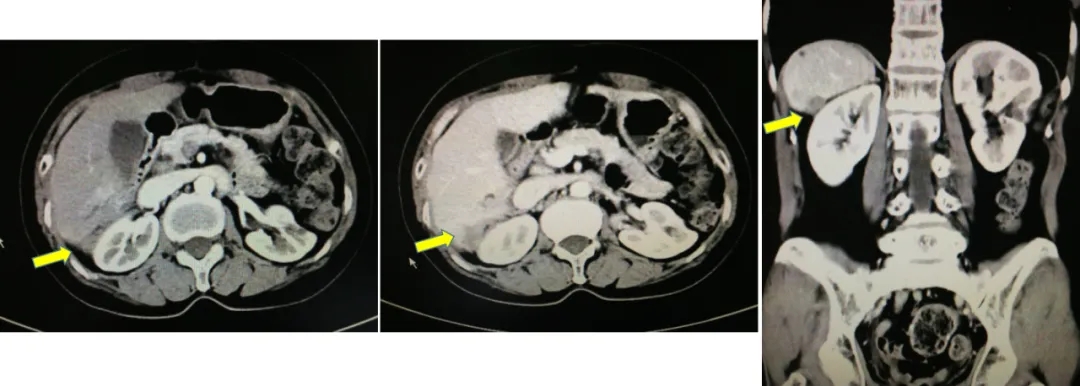

2017-10-26当地查CA125水平为46.3U/ml,2017-12-4我院查CA12水平为110.9U/ml,CT显示肝肾间隙及右肝包膜下片状影较前增大,考虑疾病复发。

CT检查结果